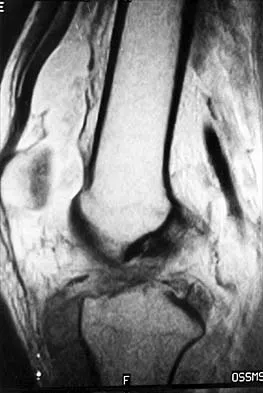

Question 49

Figure 50 shows the MRI scan of a 20-year-old female college soccer player with knee pain. What is the most likely diagnosis?

Explanation